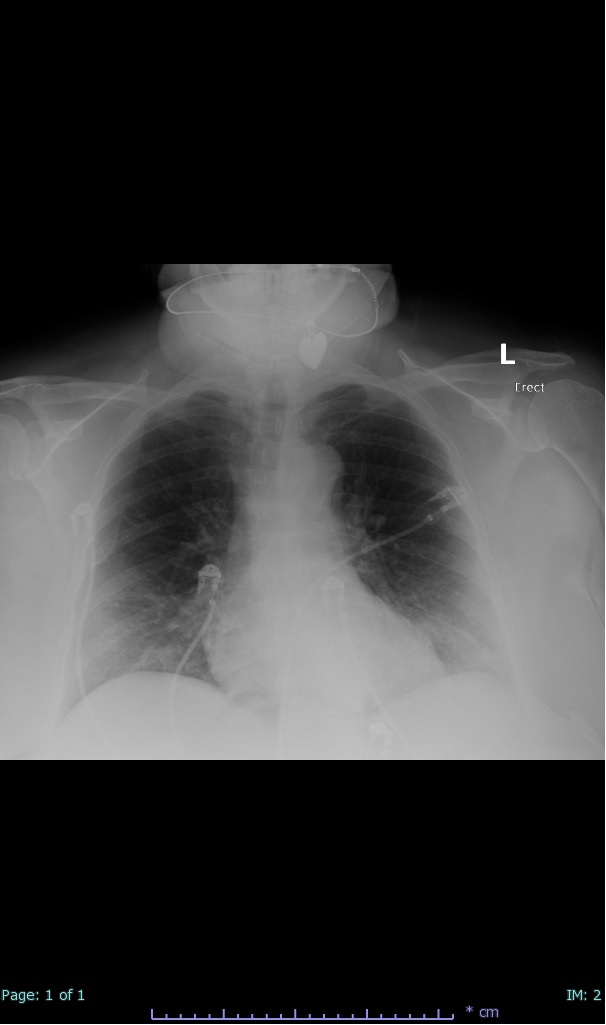

- 66% had some + CXR finding I could correlate to a CT finding

- 66% had documented exposure, rest I couldn't find either way

I'll list age decade and + exposure documented #covid19 #coronavirus #radiology #FOAMed #radres 2/17